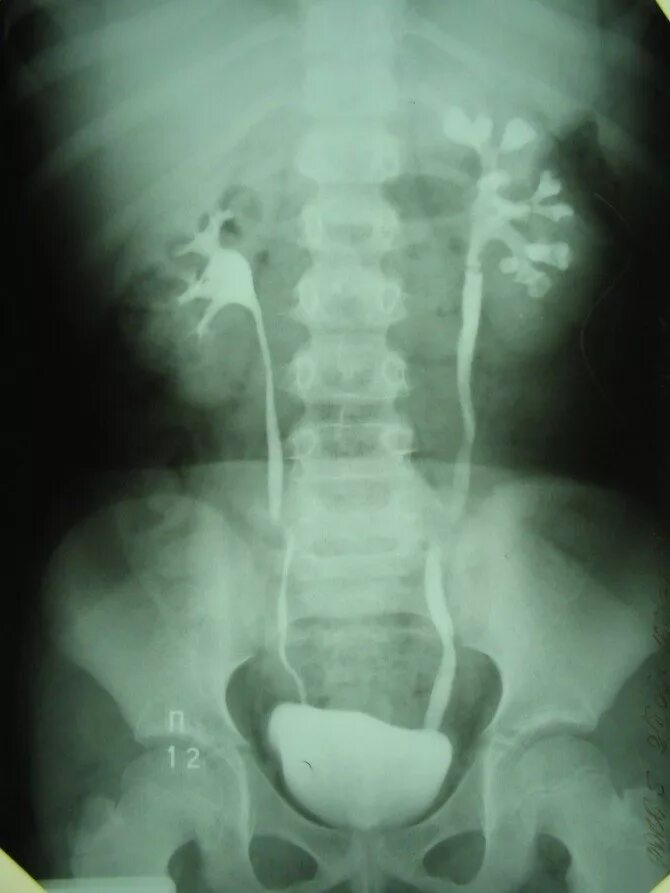

Как делается урография